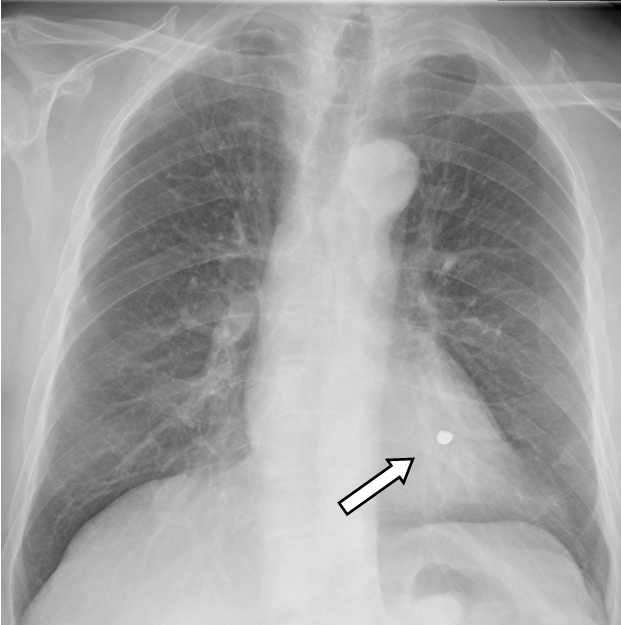

An 80-year-old male was referred to our hospital after he aspirated a tooth into his airway during a dental procedure. An 8-mm radiopaque foreign body was detected in the left lower bronchus on a chest radiograph and computed tomography scan (Figure 1) and (Figure 2). Removal by flexible bronchoscopy was attempted on the next day, but the foreign body was not found in either bronchial tree. The radiograph showed the tooth in the abdomen (Figure 3). The tooth was considered to have been expectorated and swallowed into the digestive tract. He was discharged, and one week later, we confirmed that the patient passed it.

Figure 1: An 8-mm radiopaque foreign body is seen in the left lower bronchus on a chest radiograph.